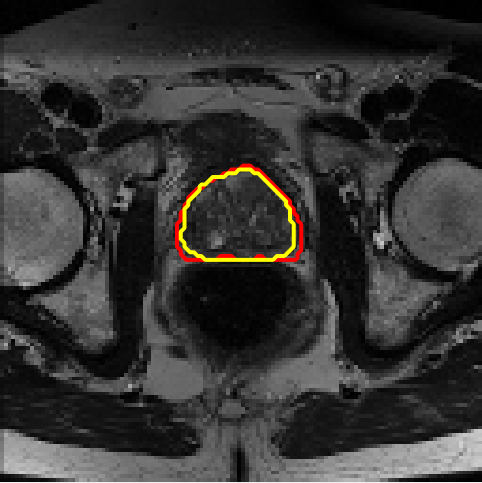

4.4 Results on PROMISE12

We assess different semi-supervised methods on the PROMISE12 dataset (Litjens et al., 2014). The PROMISE12 dataset contains 50 transverse T2-weighted MR images with the most anatomical detail. 35 and 15 cases are randomly selected for training and validation. The images were resized to 128×128128\times 128. The training dataset includes nn fully annotated images, with pixel-wise labels unavailable for the remaining 35n35-n. Table 3 presents the results. Fig. 7 offers a visual comparison of the segmentation results for different models and shows that the proposed method achieves more precise segmentation.

Figure 7: Example segmentation obtained by different methods on the PROMISE12 dataset. Red lines indicate predicted results, and yellow lines indicate ground truths.